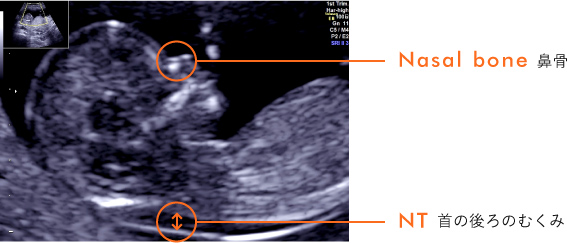

02 妊娠初期 胎児の頸部浮腫 Nt 妊娠11 13週でcheck 深谷産婦人科 医学情報

胎児の首の後ろのむくみ 浮腫 Nt とは 妊娠初期 All About

Nt Nuchal Translucency について 出生前検査 Nipt 遺伝カウンセリング 妊婦健診 エコー検査 産科 婦人科 産婦人科

胎児の首の後ろのむくみ 浮腫 Nt とは 妊娠初期 All About

胎児の首の後ろのむくみ 浮腫 Nt とは 妊娠初期 All About

胎児の首のむくみ Nt クリフム夫律子マタニティクリニック